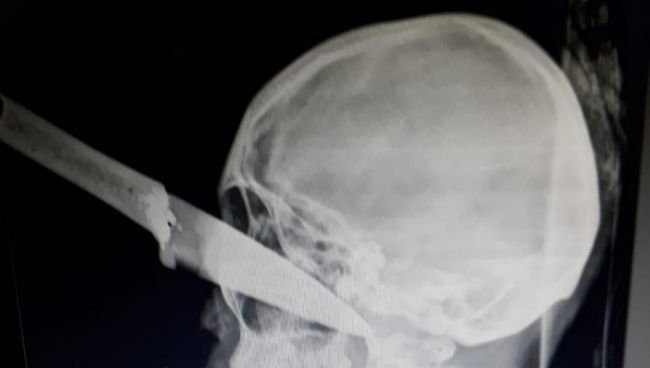

La tremenda lesión, cuyas imágenes se viralizaron

Ocurrió en El Galpón

. El fiscal penal 1 de Metán, Sergio Castellanos, tomó intervención tras las consultas policiales realizadas por un hecho de sangre ocurrido en el municipio de El Galpón, este jueves. La Fiscalía también investiga responsabilidades sobre la filtración de imágenes relativas al hecho y que se hicieron públicas.